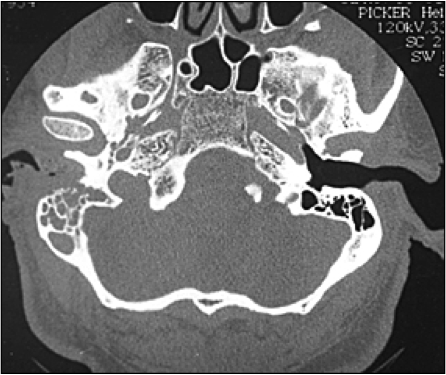

In which populations would you especially worry about MALIGNANT otitis externa (life threatening)?

Tx is hospital admit with ENT consult and IV Abx

Diagnosed on CT when pain out of proportion to exam or CN involvement seen

Elderly, diabetic, immunocompromised